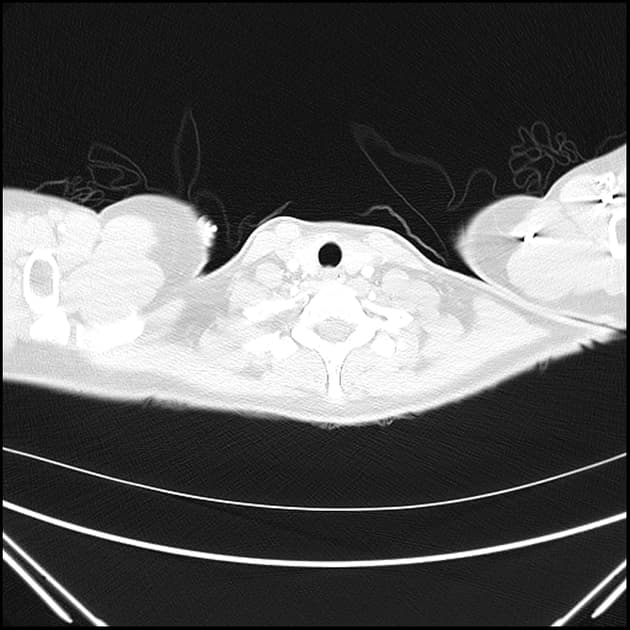

- Có thoát vị rốn nhỏ chứa mỡ.